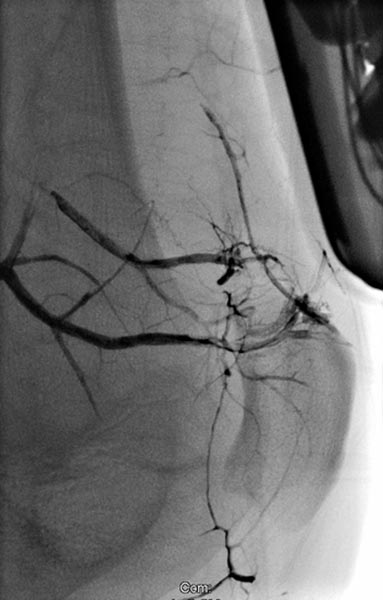

Schrittweise weitere Embolisation der hauptsächlichen Areale der arteriovenösen Malformation, hier am Knie. Der Ausguss (sogenannter Cast) durch das röntgendichte Embolisat (Ethylen-Vinyl-Alkohol-Kopolymer) zeigt den Verschluss bis in kleinste Gefäße.